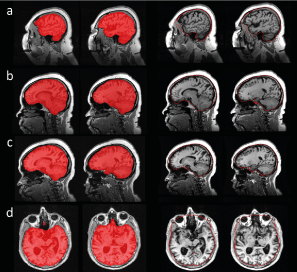

Figure 9: The middle row shows a transaxial (left), coronal (middle), and sagittal (right) slice of the mean difference between CNN-TIV and SPM-TIV estimated from the 1.5T scans in the reproducibility test set (first and second scans) in MNI space. The individual spatial normalisation transformations estimated by SPM12 during SPM12 TIV segmentation were used to transform individual difference images from patient space to MNI space. The lower row shows the mean difference between the TIVs overlaid to the MR scan of a single subject, while the MRI in MNI space is shown at the top row. The mean difference was close to 1 in lower parts of brainstem (yellow arrows) and in blood filled sinuses (red arrow), indicating that these regions were systematically included by the U-Net TIV segmentation, but excluded in SPM12 TIV segmentation.

CNN-TIV was on average about 50ml larger than SPM12-TIV. The U-Net included more inferior parts of the brain stem as well as the blood filled sinuses, in contrast to SPM12 (Figure 9). This is in line with the findings of Malone and co-workers who reported SPM12-TIV to be on average 40ml smaller than manual TIV estimates, probably due to exclusion of blood-filled sinuses by SPM12 [14]. This suggests that the CNN-TIV estimates might be closer to manual TIV segmentation than SPM12-TIV.